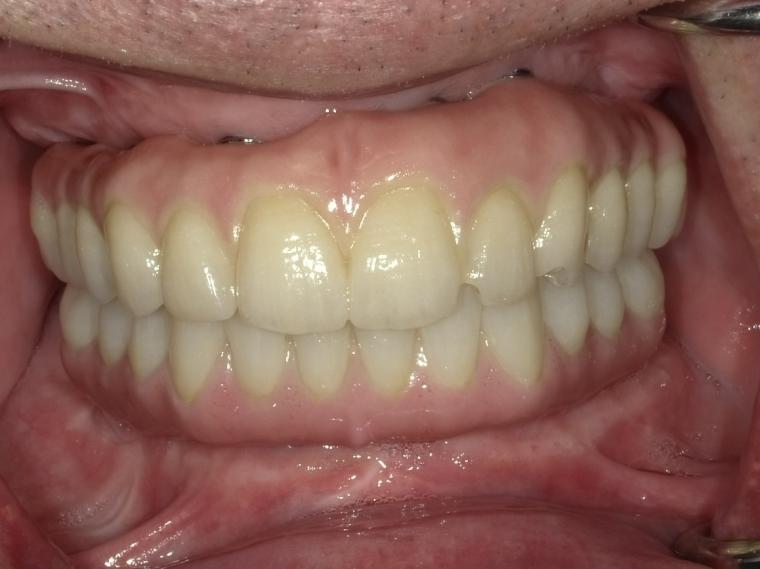

After

62歳男性/オールオン4・6症例/インプラント埋込手術

オールオン4・6というインプラント義歯での治療を選択されました。

義歯とは違い、外して洗浄する手間や、食事中にずれたりすることがないので、快適に使用されているそうです。

現在も定期検診で拝見させていただいてます。